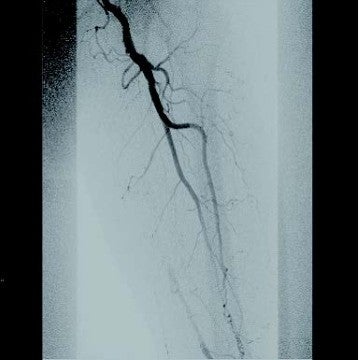

[治療] 右総大腿動脈(common femoral artery:CFA)を逆行性にエコーガイド下に穿刺。山越えで左 CFAまで6 Frガイディングシースを進めた。造影で左SFA起始部付近からベアステント遠位端のやや中枢側まで、TOSAKA分類3のISO病変があることを確認した。ところどころ病変が硬く、0.014 inchガイドワイヤーの先端2.8 gと先端12 gを順次使用して閉塞部位を突破した。PTAバルーン4 mm × 250 mmで前拡張したのち、病変部をカバーするように左SFA末梢側から左SFA起始部にかけてバイアバーン® ステントグラフト6 mm × 250 mmと6 mm × 100 mmを留置し、閉塞したベアステントをフルカバーした。バルーン5 mm × 220 mmで後拡張を実施、血管内超音波(IVUS)と造影で病変部の良好な拡張、血流を確認し手技を終了した(図3)。足関節上腕血圧比(ABI)は0.68から0.92に改善した。さらに6年が経過し、間欠性跛行の再燃があり、ステントグラフトは開存していたが(図4-1)、さらに末梢の膝窩動脈での石灰化プラークによる閉塞病変(図4-2)が原因と考えられた。アテレクトミーデバイスとDCBで膝窩動脈病変を治療して症状は消失した。run offが不良であったにもかかわらず、中枢側のステントグラフトが6年間開存していたことは特筆すべきことである。同患者については現在まで15年にわたり経過をみているが、経年的に動脈硬化が進んでおり、通常のステントやバルーンでの治療部は再治療を繰り返している。その中でステントグラフトを留置した長区間ISO病変は6年間開存を保っていたというのは、物理的に内膜過形成をシャットアウトするステントグラフトでしかみられない現象であると思われる。ISO病変に対するバイアバーン® ステントグラフトの使用が保険適用されるようになったことは、血管内治療医や患者に福音をもたらしたのではないだろうか。